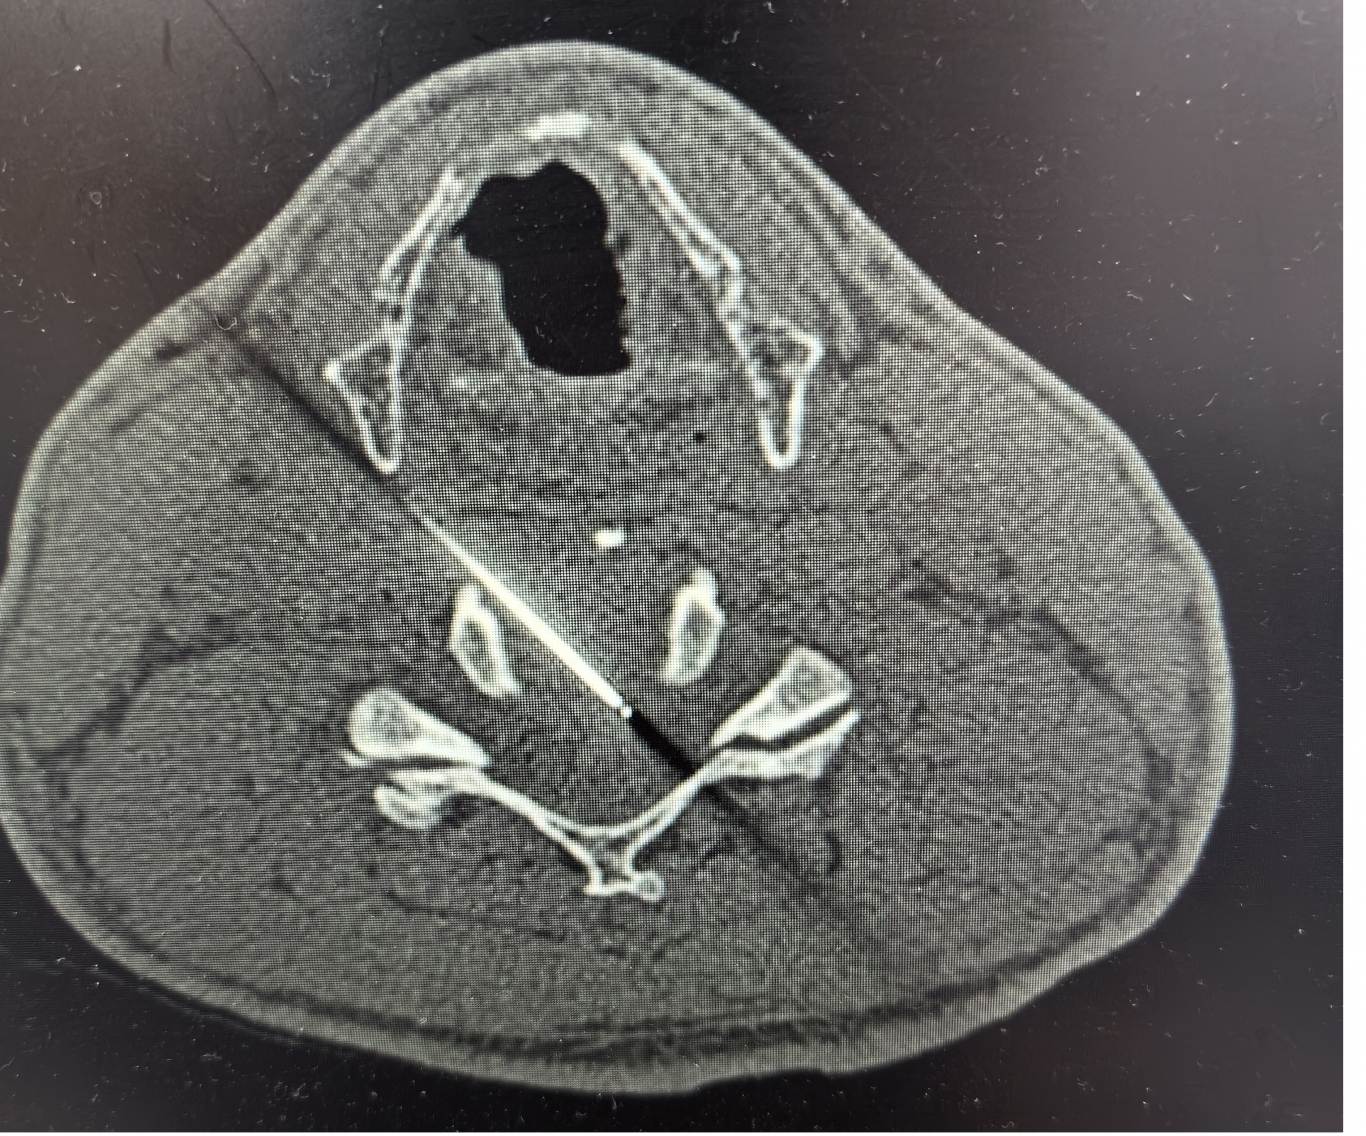

手術(shù)之后3天,黃大伯疼痛得到很好緩解,露出了許久沒有的笑容,終于可以安心躺著睡覺了,1個(gè)月后基本恢復(fù)了正常生活,6個(gè)月后復(fù)查CT發(fā)現(xiàn)突出的頸椎間盤已經(jīng)基本消失了,黃大伯一家人對(duì)治療效果非常滿意。

手術(shù)之前CT,巨大突出物 術(shù)后6個(gè)月復(fù)查CT:突出物消失